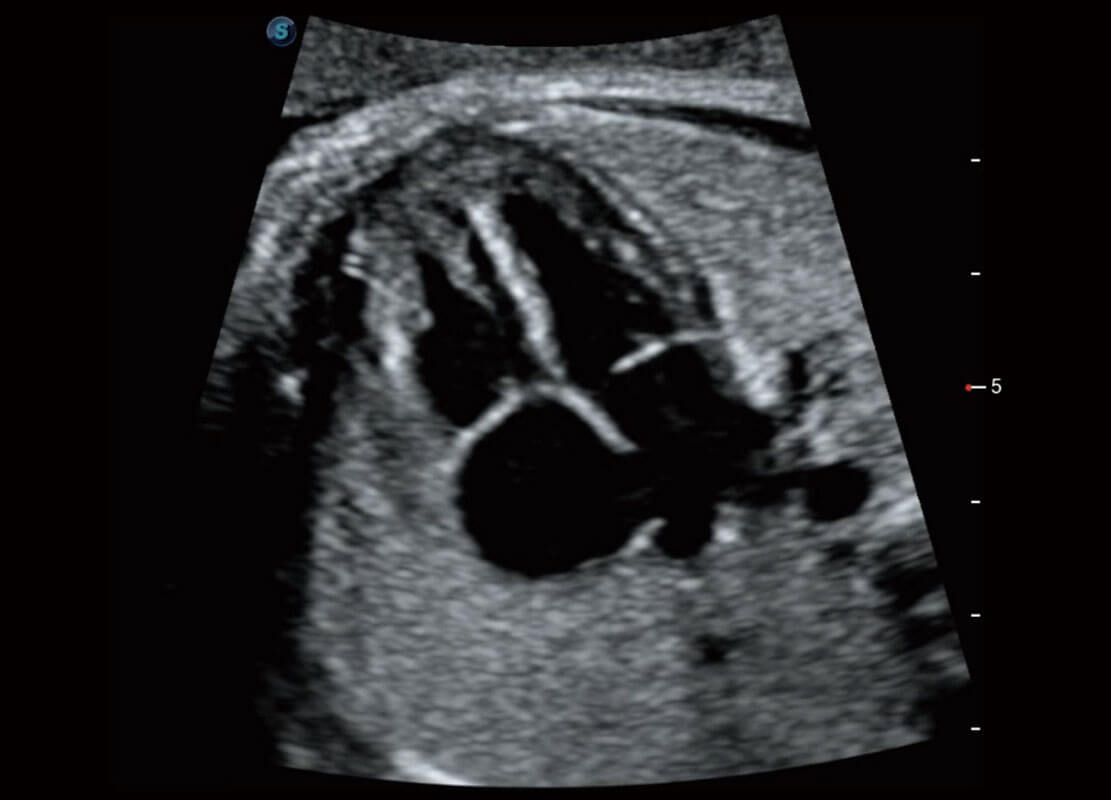

新生儿肝血管癌

新生儿脊髓圆锥

P60搭载宽频带线阵探头、宽景成像、弹性成像技术,为您提供乳腺应用方案。P60支持高频相控阵探头、线阵探头、腹部高频探头、腹部微凸探头等,丰富的探头群搭载敏感的彩色血流成像,适用于新生儿多种脏器检测要求,满足新生儿筛查需求。